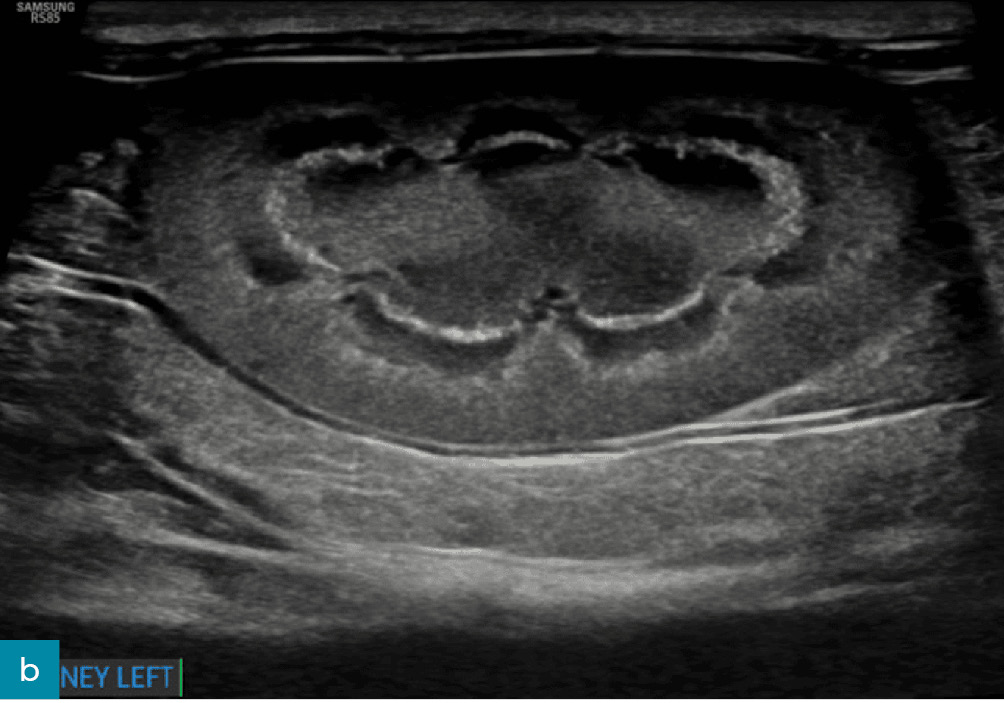

Nieregularny brzeg nerki

Nieregularne brzegi nerek (ryc. 9) mogą być związane z jednym lub kilkoma – często współwystępującymi – procesami, takimi jak zwłóknienie, stwardnienie, zanik, tworzenie torbieli albo zawał nerki.12 Nieregularny brzeg nerek jest często obserwowany w bardziej zaawansowanych stadiach przewlekłej choroby nerek i może wiązać się ze złym rokowaniem.8,15,17

Medium huguet ryc9 opt

Ryc. 9. Obraz w projekcji strzałkowej lewej nerki kota, ukazujący wyraźnie nieregularne brzegi związane z obecnością hiperechogeniczności kory nerki oraz przewlekłych zawałów kory nerkowej. Obecna jest także łagodna pielektazja.